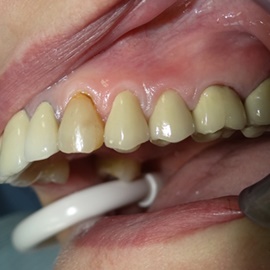

Bezzębie całkowite górne. Początkowo wykonane na mieście mosty całoceramiczne wydawały sie sukcesem, ale po roku pojawiły sie obrzęki i krwawienie z dziąseł. Pacjentka zgłosiła się do leczenia. Usunięto wszystkie zęby w szczęce. Sterowana regeneracja tkanek kości wyrostka, modelowanie kształtu i objętości tkanek miękkich, mosty porcelanowe przykręcane do implantów. Zadowalający wynik anatomiczny i estetyczny.